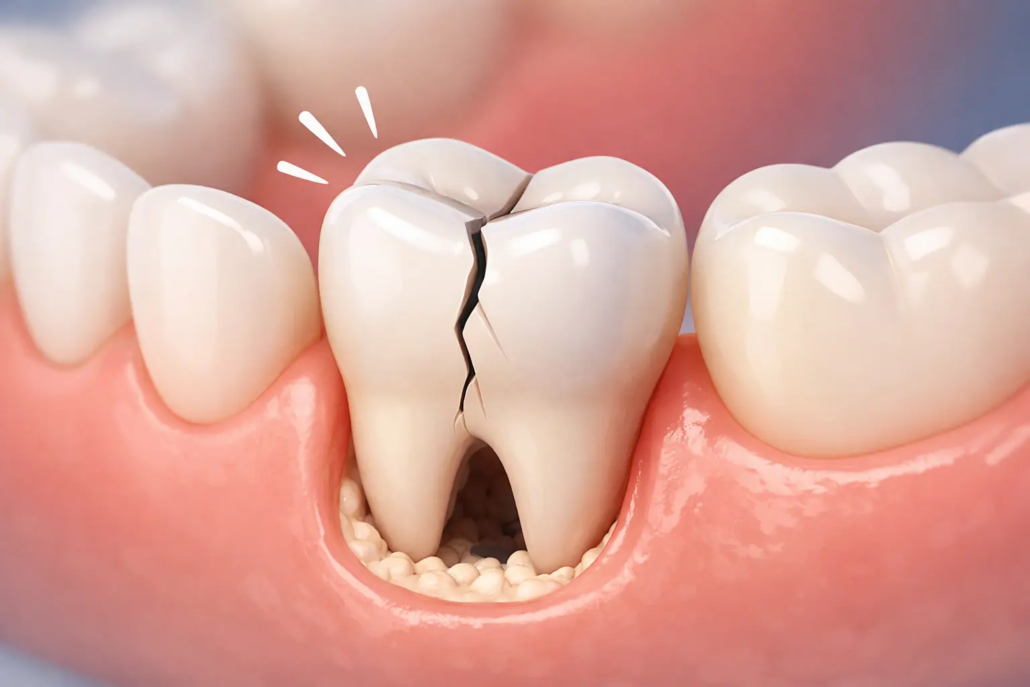

Pourquoi une dent fêlée fait mal surtout quand on mâche ?

Quand vous mordez, la dent subit une pression. Si une fissure est présente, elle peut :

s’ouvrir légèrement, irritant la dentine ou la pulpe

créer un micro-mouvement entre deux fragments de la dent

favoriser une inflammation interne (et parfois une infection si la fissure progresse)

C’est pour ça que beaucoup de patients décrivent une douleur “électrique”, courte mais intense, déclenchée par la mastication.